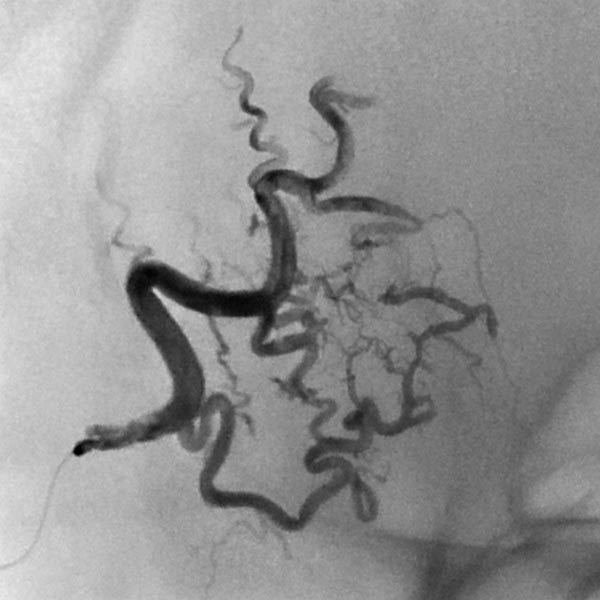

Digital subtraction angiography (DSA) with contrast injection into the right external carotid artery. The superficial temporal artery reveals a microfistulous AVM with markedly dilated feeder arteries on the right forehead with immediate venous outflow.

DSA image depicting the arterial inflow, nidus with small arteriovenous fistulae, and venous outflow of the AVM before embolization. The complete angiomorphology of the AVM, at this point untreated, is easily visible.